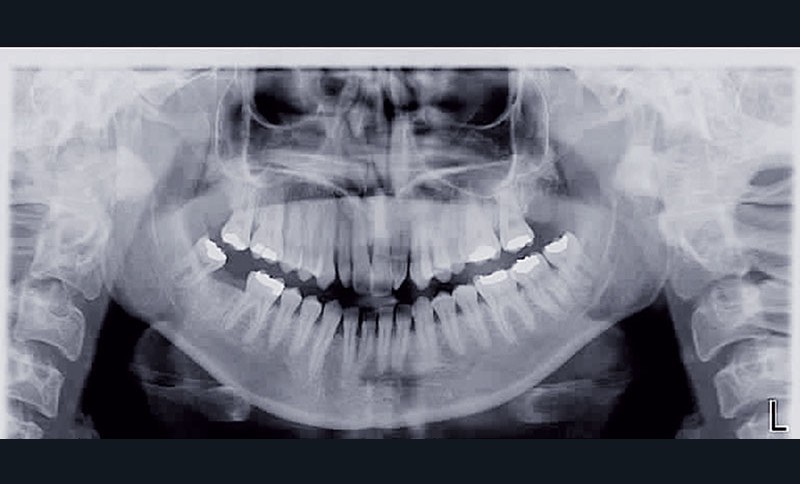

Cette patiente est venue consulter pour son occlusion inversée et ses importantes malpositions dentaires antérieures associées à la perte d’une dent et à des problèmes parodontaux.

• Malocclusion de classe III d’Angle par rétroalvéolie maxillaire,

• endoalvéolie maxillaire avec occlusion inversée antérieure et bilatérale,

• infraclusion incisive,

• fortes malpositions des incisives supérieures (dont 22 qui est en rotation axiale disto-palatine de 90°), • dysharmonie dento-dentaire (12 en « grain de riz » est aussi en rotation marginale disto-palatine de 45°),

• anomalie de la forme d’arcade maxillaire, 47, 18 et 28 sont absentes. (fig. 1 à 8), 48 est positionnée très postérieurement, quasiment au niveau de la branche montante (fig. 9 et 11).

Après assainissement parodontal, un traitement par expansion maxillaire avec vestibuloversion des incisives supérieures et mésialisation de 48 en lieu et place de 47 a été choisi. Il a été décidé d’extraire 38. Afin de permettre une reconstitution prothétique pour compenser la microdontie de 12 il est prévu de laisser un espace de part et d’autre de celle-ci, équivalent au diamètre mésio-distal de 22 soit 6,5 mm.

Consécutivement à la vestibuloversion des incisives supérieures, une aggravation de l’infraclusion incisive est attendue. Des élastiques intermaxillaires verticaux antérieurs…